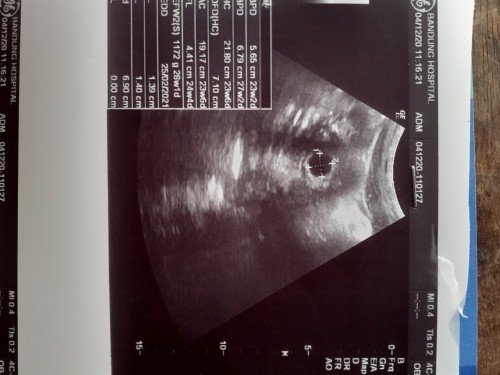

พอดีมีเลือดออกจากช่องคลอดแต่ไม่เยอะมากแค่ครึ่งของผ้าอนามัยเป็นสีชมพูอ่อนๆ พอไปหาหมอ ซาวด์ดูยังม่พบตัวเด็ก พบแต่ถุงตั้งครรภ์ แต่เลือดเริ่มไหลน้อยแล้วนะคะ แม่ๆเจอตัวเด็กตอนกี่วิคคะ บ้านนี้10week 6day ยังไม่เจอเลย #จะเป็นท้องลมไหมคะ. กังวลมากเลย

รอบแรก ตอน 5week เจอก้อนกลม ซาวด์รอบ 2 ตอน 8week น้องดิ้นแล้วนะคะ หัวใจเต้นแล้ว. อันนี้คุณแม่ 10week ยังไม่เจอน้อง ขอให้รับปรึกษาคุณหมอเลยค่ะ เป็นกำลังใจให้นะคะ